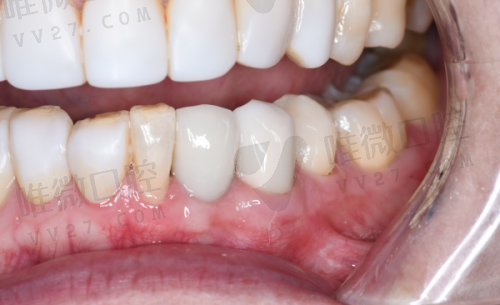

2026年在北京大学口腔医院种牙,价格主要看种植体品牌。

国产的莱顿种植牙4000元起,创英5500元起;韩国登腾5300元起;

欧美进口的就贵了,瑞士ITI 9020元起,德国费亚丹11200元起,瑞典诺贝尔11700元起。

半口种植12万起,全口种植21万起。

这里要提醒大家,价格还包含手术费,比如种一颗瑞士ITI,种植体1.2万+手术费5000元,总价1.7万左右。偷偷告诉你,如果预算有限,可以考虑国产种植体,现在技术也特别成熟了!